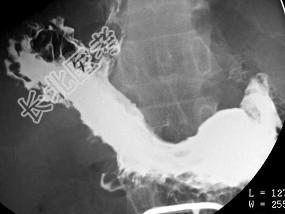

- 单项选择题男,59岁, 进行性吞咽困难半年,结合图像, 最可能的诊断为 ( )

D、食管癌

E、贲门癌侵及胃底、食管下段